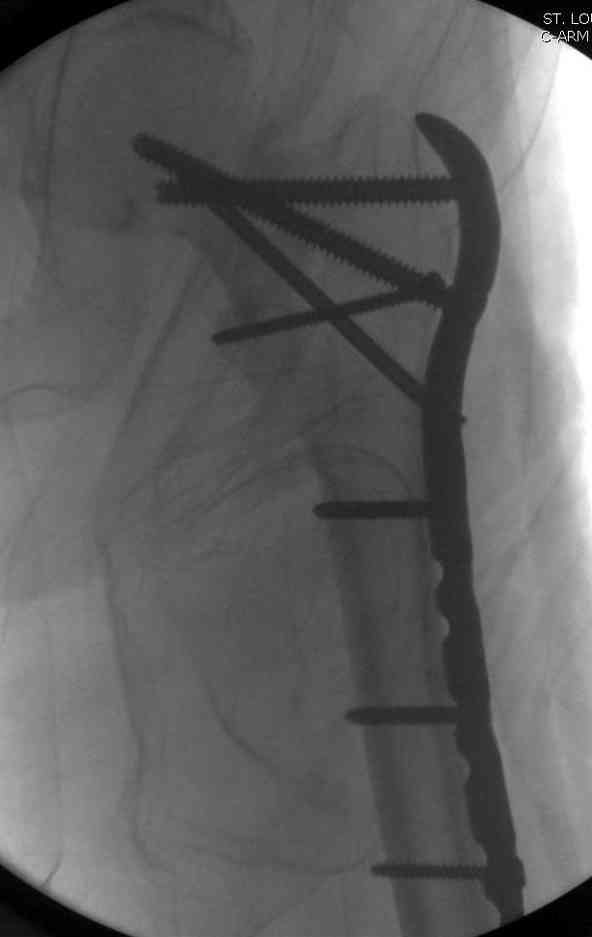

Адекватная фиксация достигается длинным 95 градусным Blade Plate, где клинок пластины, связывая головку со средней трети бедра, создал бы условия для сращения.

Другой вариант пластины, это Synthes Proximal Locking Plate предназначенный для лечения прксимальных переломов бедра, где три шурупа: два 7.3 мм, введенных в головку под углом 95, 120 и 5.0 мм в 130 градусов, создают угловую стабильность.

Профилактику прорезывания шурупов в кости можно добиться введением в отверстие цемента, потом проведением шурупа, цемент, застывая, удерживает шуруп в правильном положении.